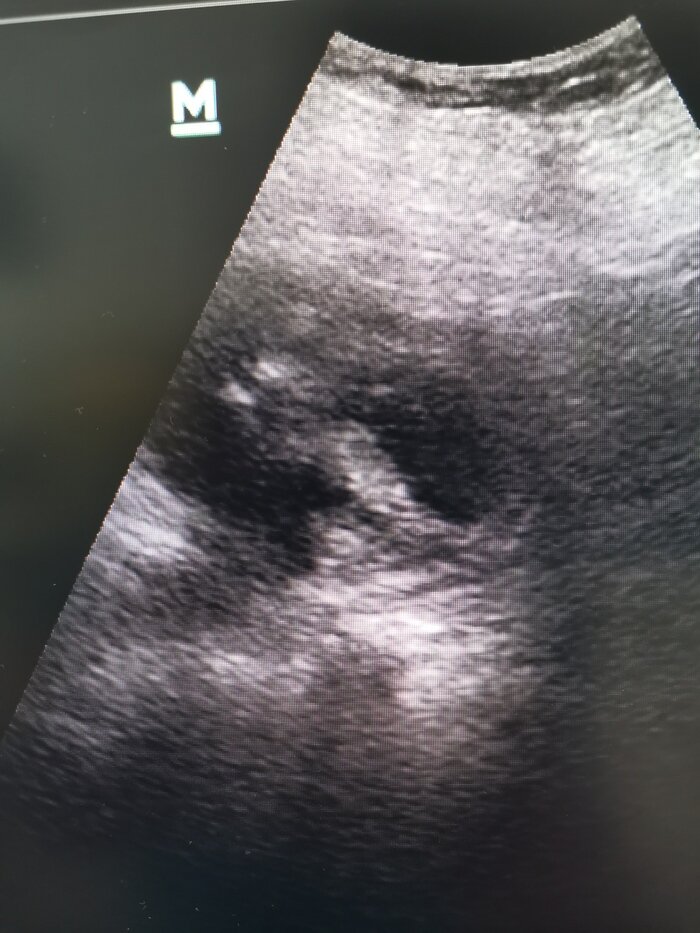

Оказывается, пациент уже месяц страдает лихорадкой, был на приёме у терапевта и принимал противовирусные препараты. Эффекта ноль. Продолжает болеть дома. И вот решается вызвать скорую. И оказывается на кушетке в тёмном помещении (УЗИ кабинет) рядом со мной. Туда мы отправились, потому что причин у длительной лихорадки множество. Я, как уролог, хорошо знаю парочку из них. На УЗИ видны вполне обычные почки (не стал фоткать), а по нижнему сегменту левой почки гетерогенное, солидно-кистозное, отграниченное, с ровным, не чётким, гипоэхогенным контуром образование около 6 см (см фото). В подобной ситуации может быть несколько интерпретаций: нагноившаяся киста почки (полость с гнойной мочой), рак, карбункул (гнойник на почке). Исход следующий: Пациент госпитализируется для проведения КТ почек с контрастом (чтобы установить более точный диагноз) и пробной антибиотикотерапии. В итоге хвалю волю случая и себя за проделанную работу. Если интересно, чем закончилась данная история, жмём плюс и оставляем комментарии. Дальше - больше.